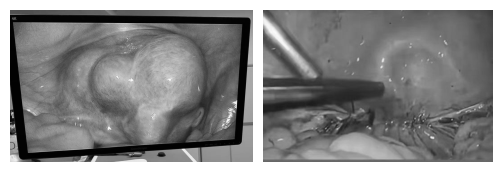

王女士是一名多发且巨大子宫肌瘤的患者。多年来,她默默忍受着疾病带来的种种不适:月经量过多导致严重贫血,时常头晕乏力;肌瘤压迫膀胱和肠道,让她饱受尿频、腰酸之苦,生活质量大打折扣。在医生的专业建议下,她最终选择了腹腔镜全子宫切除术。术后康复顺利的她,不仅身体日渐轻松,更希望用自己的经历提醒更多女性朋友:面对子宫肌瘤,科学判断、及时干预至关重要。

王女士表示,随着医学技术发展,腹腔镜微创手术已十分成熟,创伤小、恢复快,让她能更快回归正常生活。她鼓励正在犹豫的姐妹们:不要因恐惧或“舍不得”而忍受痛苦,听从专业医生建议,该手术时就手术。及时止损,才能为身体减负,为生活松绑。